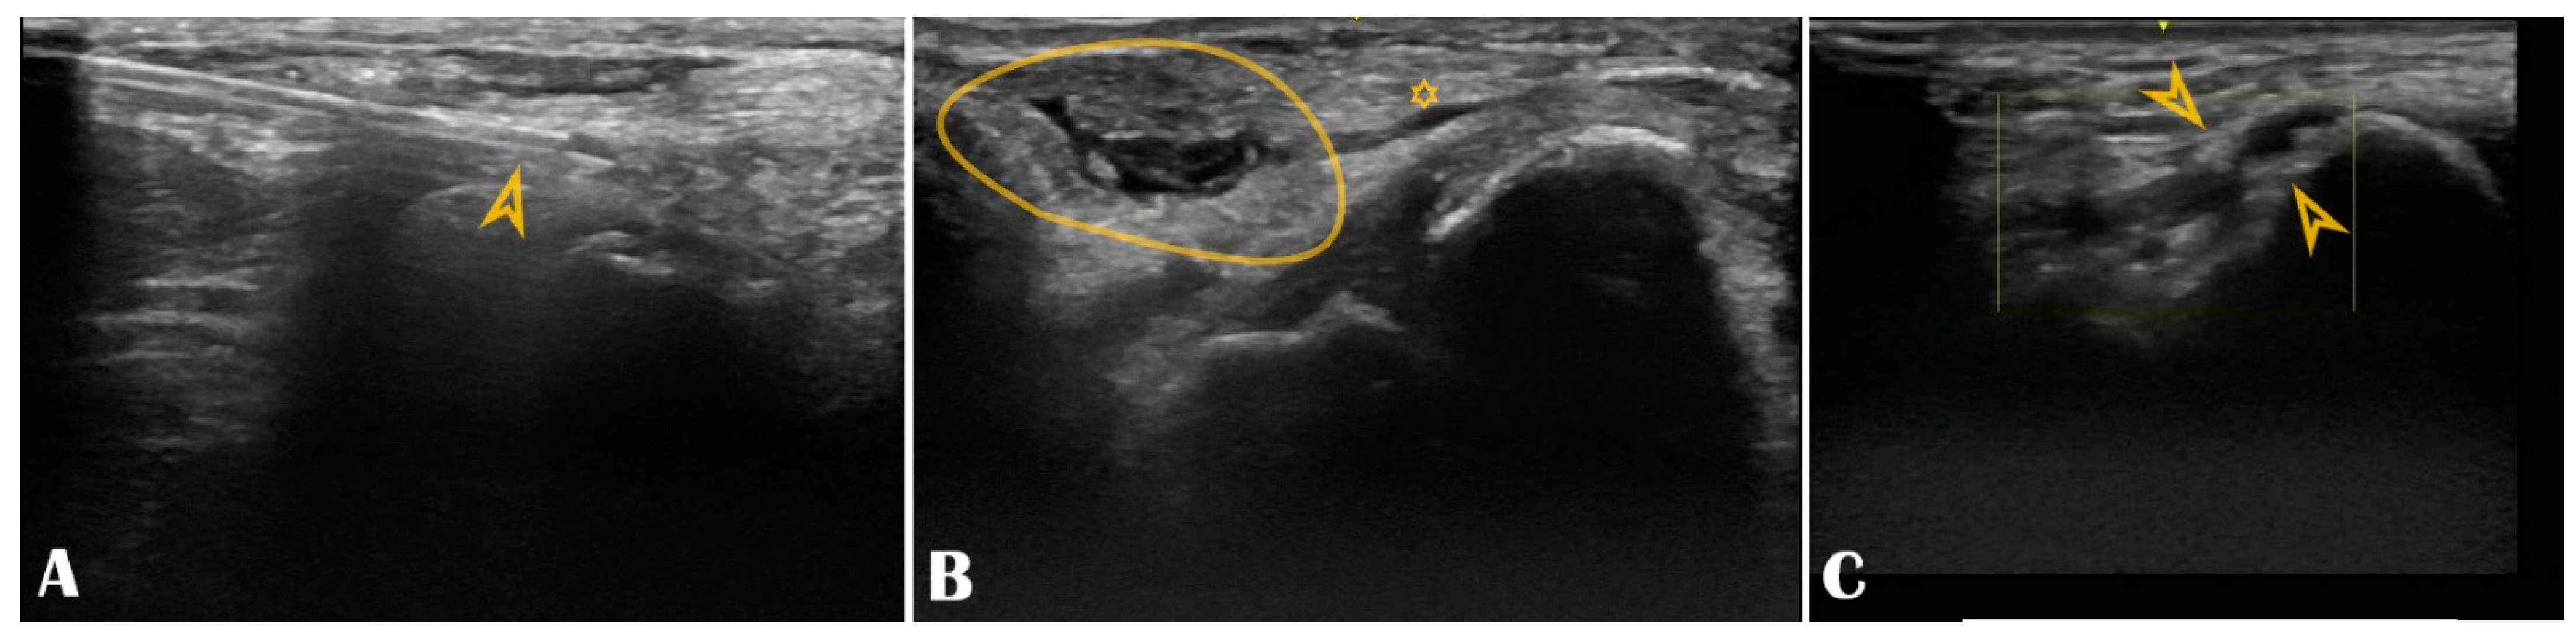

Figure 6.

Panel (A): The puncture needle is clearly seen in the longitudinal axis (arrowhead); Panel (B): Hematoma (circle) compressing the distal radial artery (asterisk); Panel (C): The distal radial artery is with stenotic atherosclerotic plaques (arrowheads).